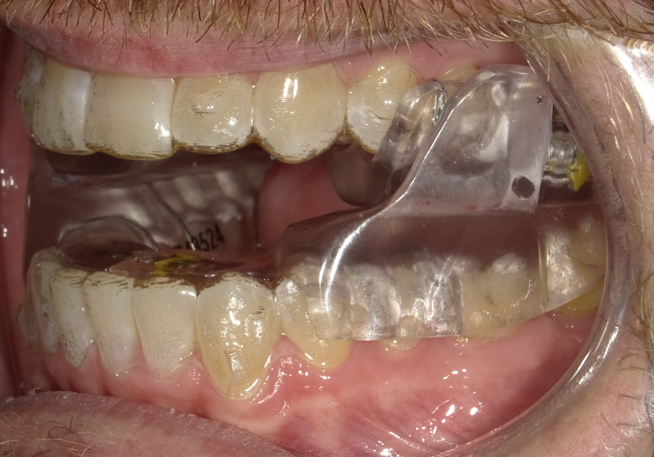

Fig 8. The appliance worn during treatment, anterior view (Fig 8), right side view (Fig 9), left side view (Fig 10), and upper arch view (Fig 11).

Figure 8

Fig 9. The appliance worn during treatment, anterior view (Fig 8), right side view (Fig 9), left side view (Fig 10), and upper arch view (Fig 11).

Figure 9

Intraoral scans were taken to document the patient's entire palate and bite registration. Scans were sent to the clinical team for the fabrication of a clear aligner/sleep appliance for the patient to wear; the chosen appliance fits over clear aligners, regardless of the tray number the patient may need (Figure 7 through Figure 11).

After the appliance was delivered, additional photographs were taken with the camera to ensure that the appliance was delivered as intended, to document the case, and to show the patient the ideal fit of the appliance in his mouth as instructions were reviewed with him.